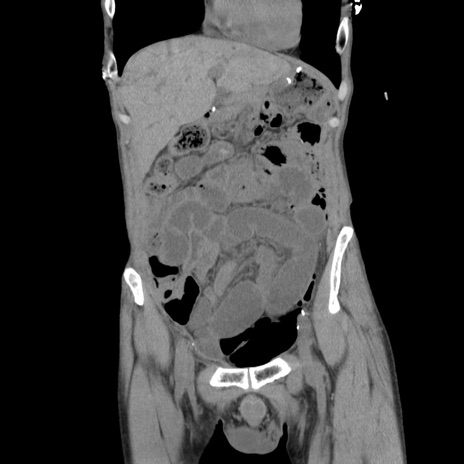

症例11(冠状断像)

【症例】 60歳代男性

【主訴】 下腹部痛

【現病歴】 本日夜中より下腹部痛の症状認め、受診。

【既往歴】 膀胱癌(膀胱全摘+尿管皮膚瘻術) 、胃癌術後

【身体所見】 BT 35.3℃、PR 58/min、BP 136/98mHg、腹部平坦、軟、腸蠕動音±、ストマ留置あり、左上腹部~正中部に圧痛あり、反跳痛なし。

【データ】WBC 5100、CRP0.01